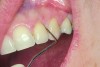

The presence of keratinized tissue around teeth and implants and its role in periodontal maintenance is somewhat controversial. It has been suggested that 2 mm of keratinized tissue is important to maintain gingival health around teeth.16 Minimal recession also facilitates maintenance by the therapist and plaque control by the patient (Figure 4 and Figure 5). Keratinized tissue around implants is also important. Chung et al17 completed a retrospective study examining the barrier function of keratinized tissue around dental implants. They examined 339 endosseous dental implants in place for at least 3 years in 69 patients and found that when an adequate band of keratinized tissue was present, less inflammation and plaque accumulation occurred (Figure 6 and Figure 7). Although there was no correlation to bone loss, there was improved comfort while cleaning the sites with keratinized tissue versus those areas that lacked keratinized tissue.

Geurs et al18 also found that establishing a soft-tissue barrier sheltered the underlying osseous structures and the osseointegration around the implant body. Kim et al19 conducted a study with 276 implants placed in 100 patients and demonstrated that cases with insufficient keratinized gingiva near the implants showed increased risk of gingival recession (Figure 8) and crestal bone loss. It is critical that keratinized tissue be evaluated around both teeth and implants, and when there is an insufficient amount, treatment should be considered to increase the thickness and overall health.

Fig 4. Severe recession visible on teeth Nos. 29 and 30.

Figure 4

Fig 5. Teeth Nos. 29 and 30 following connective tissue grafting showing minimal recession and improved tissue health.

Figure 5

Fig 8. The implant on No. 23 4 years later with no maintenance care, showing increased inflammation and recession.

Figure 8